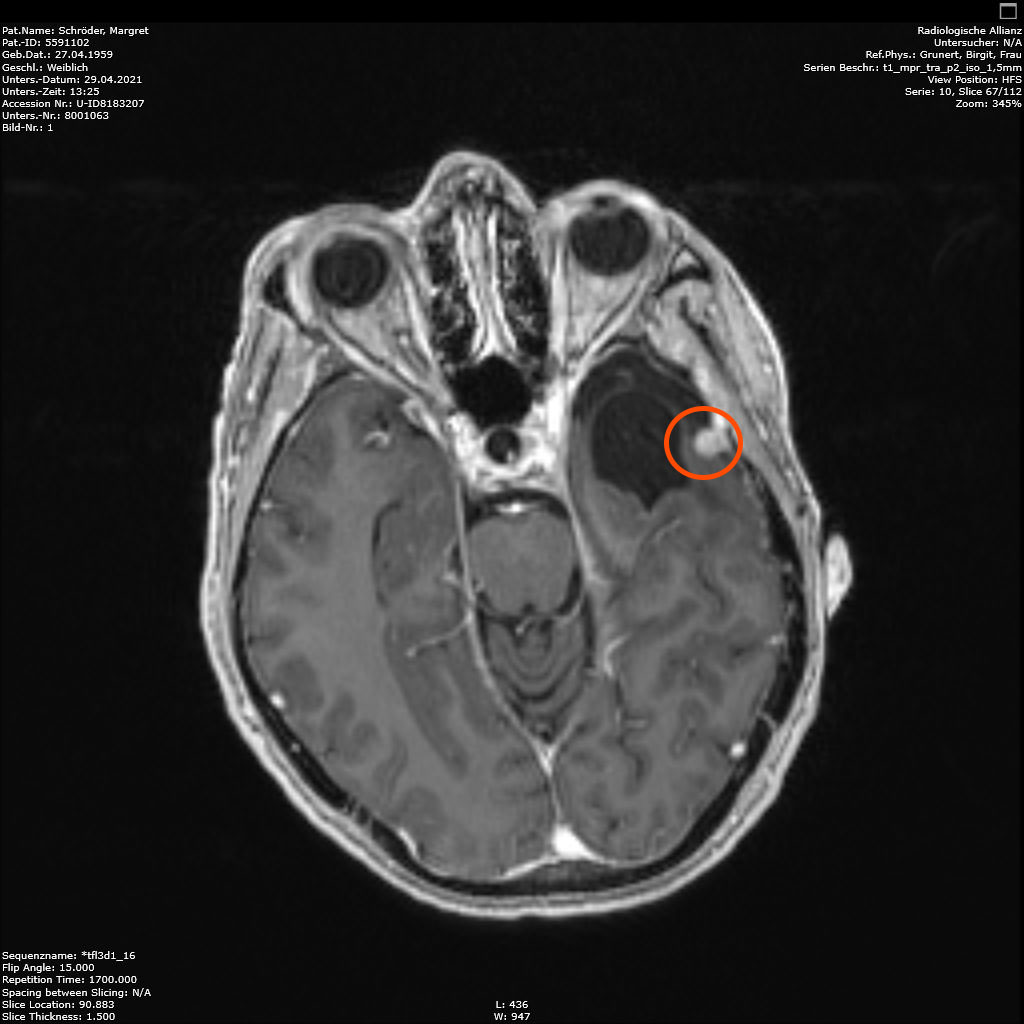

April 2021:Leider keine Veränderungen

Am 29.4.2021 war ich zum Kontroll-MRT drei Monate nach der hochmodernen Strahlentherapie, dem Gamma-Knife. Leider ist das Ergebnis: den Tumor hat diese Behandlung nicht beeindruckt, keine Änderungen zu erkennen. Der Arzt schlägt eine weitere Kontrolle in 6 Monaten vor. Ich finde es etwas schwer, dieses Ergebnis einzuordnen. Aber so ist es nunmal. Vielleicht ist es ja normal, und wird erst später gut (siehe Punkt 4).

Zu meinem Geburtstag am 27.4. habe ich sehr schöne Geschenke bekommen und kann mich auch über meinen bunten Garten freuen, im Herbst gab es ein Tulpen-Sonderangebot, dem konnte ich nicht wiederstehen! Und nun ist das Ergebnis zu sehen. Am 28. April war wieder mal MRT-Termin. Leider hat es an dem Tag eine Vertretung des auswertenden Arztes gegeben, die Ärztin war super freundlich aber hat keine ganz konkreten Aussagen machen können, aber sie hat mir 2 CDs gebrannt, ich konnte eine gleich bei den Neurochirurgischen Ambulanz abgeben und eine mit nach Hause nehmen. Mein Blick auf die Bilder hat eine nazu unveränderte Lage gezeigt.

Heute war der Termin beim Chirurgen, leider schon um 9:00 Uhr und natürlich wollte ich die knapp 20 km mit dem Rad zurück legen, Stephan wollte gerne mitkommen. Leider war die bereits abgegebenen CD nicht eingelesen worden und so musste erstmal die Datenverarbeitung arbeiten und wir warten, bis wir eine Auskunft bekommen konnten. Fazit: Der bestehende Tumor ist kaum gewachsen. Aber es hat sich leider ein 2. Fund ergeben, sehr klein aber deutlich sichtbar. Aber Maßnahmen sind erstmal nicht notwendig.